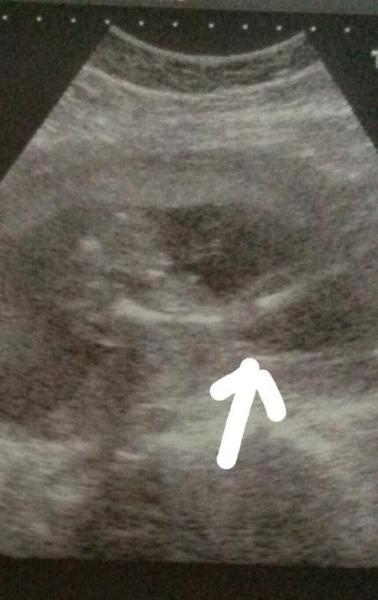

Hallo ihr lieben Hab mir heute mein US bild von gestern 20ssw nochmal genau angeschaut der Arzt sagte nämlich 85% junge. Könnte es auf dem Bild ein kleines Pracht Exemplar sein? :-) kann man dem outing schon glauben?

Bild zu junge? - Schwanger - wer noch? Rund um die Schwangerschaft

Ich würde sagen, deutlicher geht's nicht mehr. Definitiv Junge. LG

Zu undeutlich, sorry. Meine beiden Jungs waren sehr eindeutig... LG Lilly